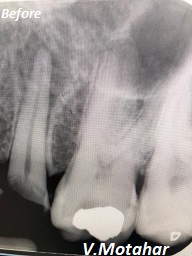

Root Canal Treatment on a Premolar tooth!

before

after